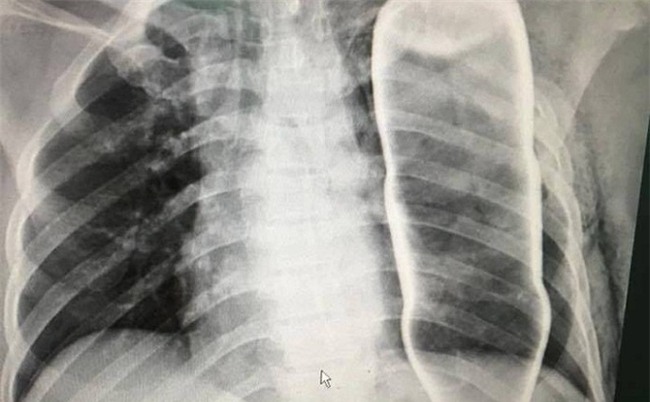

Hình ảnh chụp X - Quang vỏ chai thủy tinh trong lồng ngực bệnh nhân B. |

Sau khi bị ngã cầu thang, người đàn ông bị dị vật chưa xác định đâm vào vùng lõm xương đòn, gây khó thở. Qua chụp X quang và Citi, các bác sỹ tá hỏa phát hiện một vỏ chai thuỷ tinh còn nguyên vẹn đang nằm gọn trong lồng ngực bệnh nhân.

Ngay sau đó, các bác sỹ đã tiến hành chụp X Quang, Citi và vô cùng kinh ngạc khi phát hiện một vỏ chai nước khoáng đang nằm gọn trong ngực của bệnh nhân B.